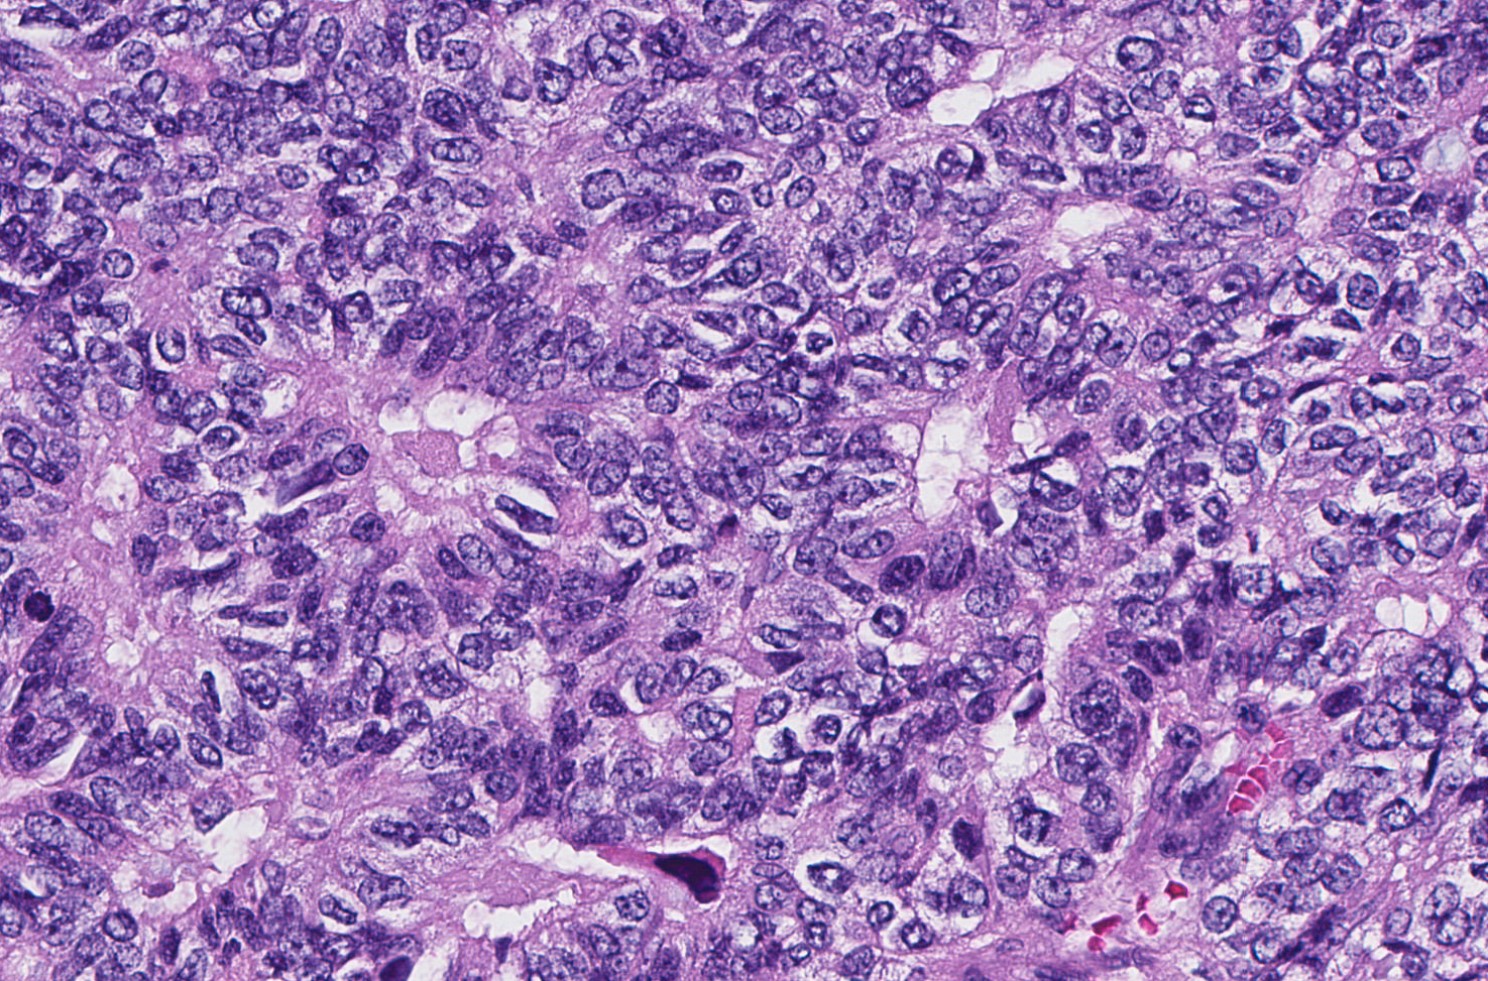

- Delicate papillary fronds with fibrovascular cores lined by cuboidal to columnar epithelial cells with low to intermediate grade atypia

- Low mitotic activity (average 3 mitoses per 10 high power fields [HPFs]) (Am J Surg Pathol 2011;35:1)

- High grade invasive carcinoma with EPC features (Histopathology 2015;66:740, Histol Histopathol 2019;34:137)

- High grade cytologic atypia with nuclear pleomorphism, frequent mitotic figures (mean mitotic activity 22 per 10 HPFs) and occasional necrosis

- More likely to be ER- or triple negative

Microscopic (histologic) images

Contributed by Kristen E. Muller, D.O. , Mariel Molina Nunez, M.D. and Julie Jorns, M.D. (Case #518)